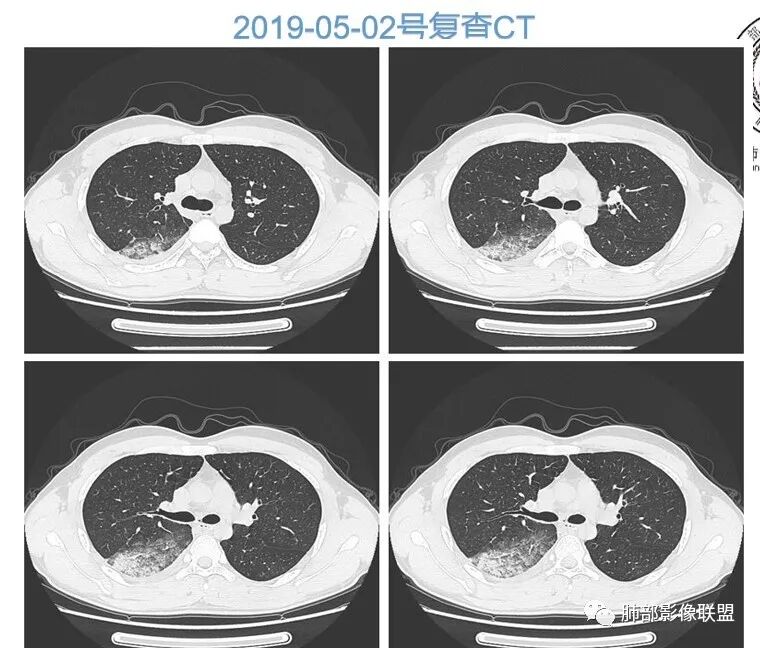

青年男性,急性病程,首次CT实变周围伴磨玻璃,边缘模糊,4天后病变明显进展大片状实变,边缘部可见磨玻璃影,内见支气管气象。考虑感染性病变,支原体?病毒?

初次右肺下叶斑片状磨玻璃及实变影,4天后复查明显进展,大片实变及磨玻璃,细网格,下叶近段支气管壁增厚,扩张,无胸腔积液,考虑社区获得性肺炎,病毒性肺炎?

青年男性,4天前受凉咳嗽咳痰,影像表现:第一次ct示右肺下叶斑片影,边缘模糊,有晕征,第二次ct示右肺下叶大片状影,部分实变,边缘见磨玻璃模糊影,以胸膜下分布为主,与胸膜呈糊墙改变,两次复查,较前进展,白细胞不高,中性粒偏高,常规考虑感染性病变,病毒性肺炎可能,其他不排,建议病原体等相关检查。

青年男性,咳嗽咳痰发热4天,急性起病,抗感染治疗效果不佳,白细胞计数降低。第一次CT:右下叶斑片实变影伴磨玻璃影,边缘模糊。4天后复查CT:病变快速进展,右下叶大片实变影,内可见支气管充气征,边缘模糊,可见腺泡结节,叶间裂膨隆。考虑:大叶性感染,叶间裂膨隆,肺克?军团、病毒性肺炎无法除外。

患者青年男性,急性起病且使用抗菌素治疗后仍快速进展,主要症状表现为咳嗽、咳痰、畏寒、发热4天。血常规:白细胞及淋巴细胞降低。胸部CT:右下肺背段+基底段可见实变+GGO+支气管充气征,病灶位于胸膜外带下比靠近肺门处重,支气管壁未见增厚。诊断首先感染性疾病,腺病毒性肺炎可能性最大。